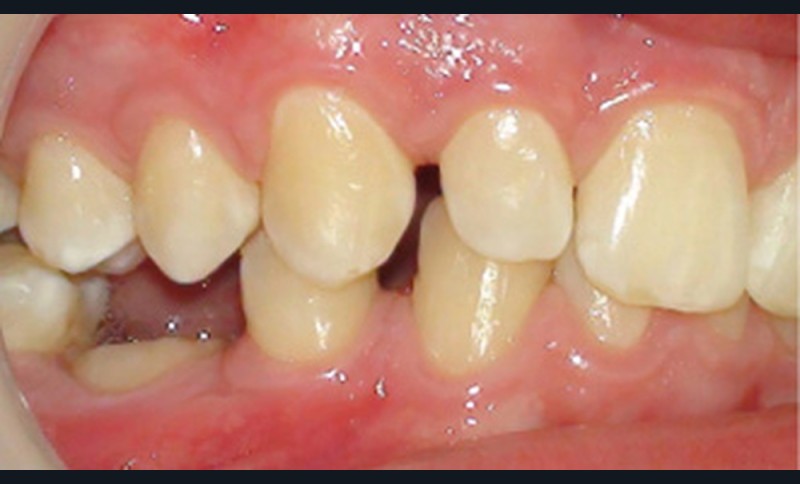

L’infraclusion de la molaire temporaire, et dans son cas extrême sa réinclusion, est le résultat d’une ankylose de la dent. Cette dent ne pourra plus suivre la croissance de l’os maxillaire ou mandibulaire et ainsi le plan d’occlusion. La molaire temporaire ne présentant pas de germe définitif sous-jacent, elle s’ankylose fréquemment à un stade plus ou moins avancé de l’individu et de la croissance des maxillaires.

D’un point de vue histologique, dans l’ankylose dento-alvéolaire, il existe une continuité de tissus durs (os-cément) avec rupture du ligament alvéolo-dentaire, précédée par une disparition locale des éléments épithéliaux de Malassez, isolants de la gaine péri-dentaire [1]. Il en résulte une résorption de la racine dont la vitesse correspond à la vitesse du remodelage osseux. Ce processus est défini comme « résorption de remplacement », l’os prenant la place du desmodonte et de la racine dans la zone ankylosée [2]. Lorsque…